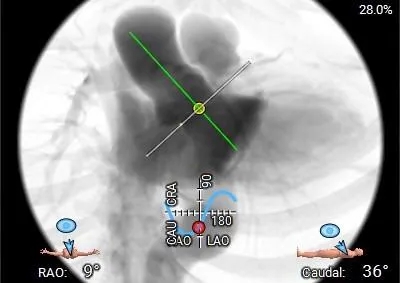

工作体位

右窦居中

左冠切线

左右重叠